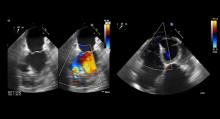

Methods: This video shows a 60-year-old female with right coronary artery occlusion, who developed a large posterior myocardial infarction with a 2.5 cm posterior ventricular septal rupture and a 2:1 left to right shunt.

Results: After a full sternotomy, the ascending aorta, superior vena cava, and inferior vena cava were cannulated. Antegrade and retrograde blood cardioplegia was used. The left ventricle was opened next to the posterior papillary muscle. The authors identified the mitral valve and aortic valve, and then found a posterobasal ventricular septal defect of 2.5 cm. The authors used interrupted 2-0 polyester mattress sutures with teflon felt from inside of the right ventricle to the outside of the left ventricle. The sutures were then passed through a Dacron patch and seated the patch. After this, the left ventriculotomy was repaired using a triple patch of bovine pericardium layers on either side of a Dacron patch ("empanada"). The authors placed interrupted 2-0 polyester sutures with teflon felt around the left ventricular free edge and then passed them through the triple patch. The patch was secured only after careful and adequate de-airing of the ventricle was performed. The postoperative echo showed no residual VSD.